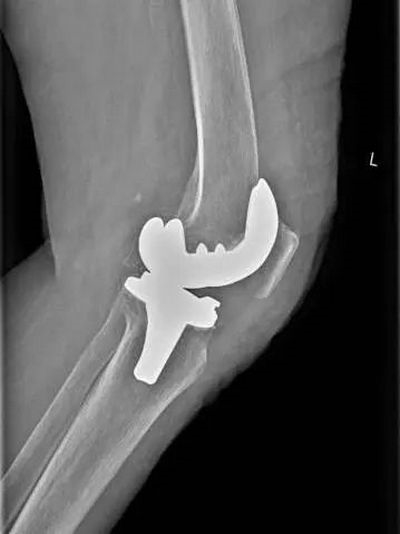

术后检查

术后践行ERAS快速康复理念,指导患者屈伸活动膝关节,并结合我院康复的优势,对患者床旁进行康复锻炼,术后第3天患者膝关节即可屈曲90°,王奶奶每次见到医师都赞不绝口。

徐明杰主任说到,膝关节表面置换术是指使用膝关节置换器械,做股骨髁、胫骨平台截骨,去除磨损的软骨和多余的骨赘,用钛或钴铬钼合金和高分子聚乙烯进行关节表面置换。